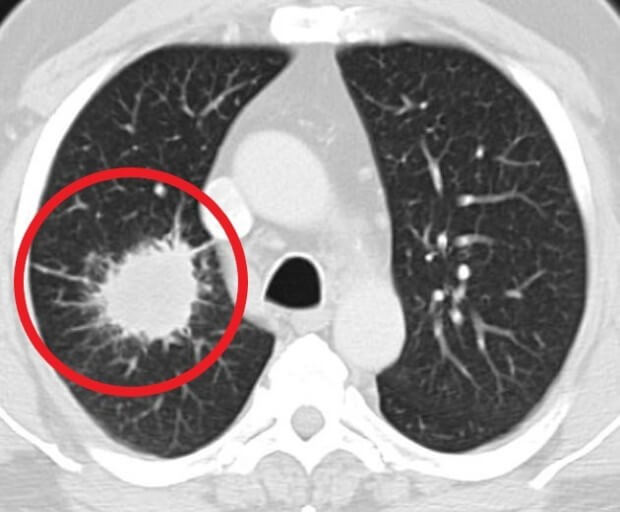

폐암 초기증상 : 폐암 4기 생존율은?

숨 쉬는 순간마다 위협하는 무서운 적, 폐암. 전체 암 사망 원인 1위를 차지하며, 진단 후 5년 내 사망률이 7~80%에 달하는 치명적인 질병입니다. 하지만 조기 발견 시 90%라는 놀라운 완치율을 기대